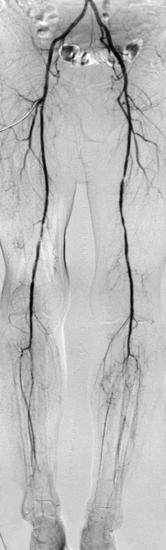

Computertomografie:

Für die Gefäßuntersuchung steht ein moderner 128-Zeilen-Computertomograf (Siemens Somatom Edge) zur Verfügung. Dieser kann bei einer räumlichen Auflösung von bis zu 0,3 mm kleinste Veränderungen nachweisen. Zur Darstellung der Gefäße wird dazu ein jodhaltiges Kontrastmittel verwendet, welches meist in eine Vene des Armes mit Hilfe einer Spritzenpumpe verabreicht wird. Die Untersuchung selbst dauert weniger als eine Minute.

Aus den dabei gewonnen Schnittbildern sind computergestützte 2D- und 3D-Rekonstruktionen aller Regionen des Gefäßsystemes herstellbar. Dieses Untersuchungsverfahren kommt in unserem Zentrum bei der Diagnostik – Erweiterungen der Bauchschlagader oder andere Gefäße, Durchblutungsstörungen aufgrund von Gefäßeinengungen oder Verschlüssen sowie der Therapieplanung und Therapiekontrolle – zum Einsatz. Einen wichtigen Stellenwert hat die Computertomografie auch bei allen akuten Gefäßerkrankungen und Gefäßverletzungen.